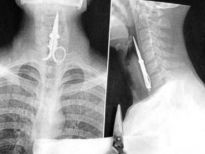

Şoke eden röntgen filmleri

Bu röntgen filmleri görenleri şaşkına çeviriyor!